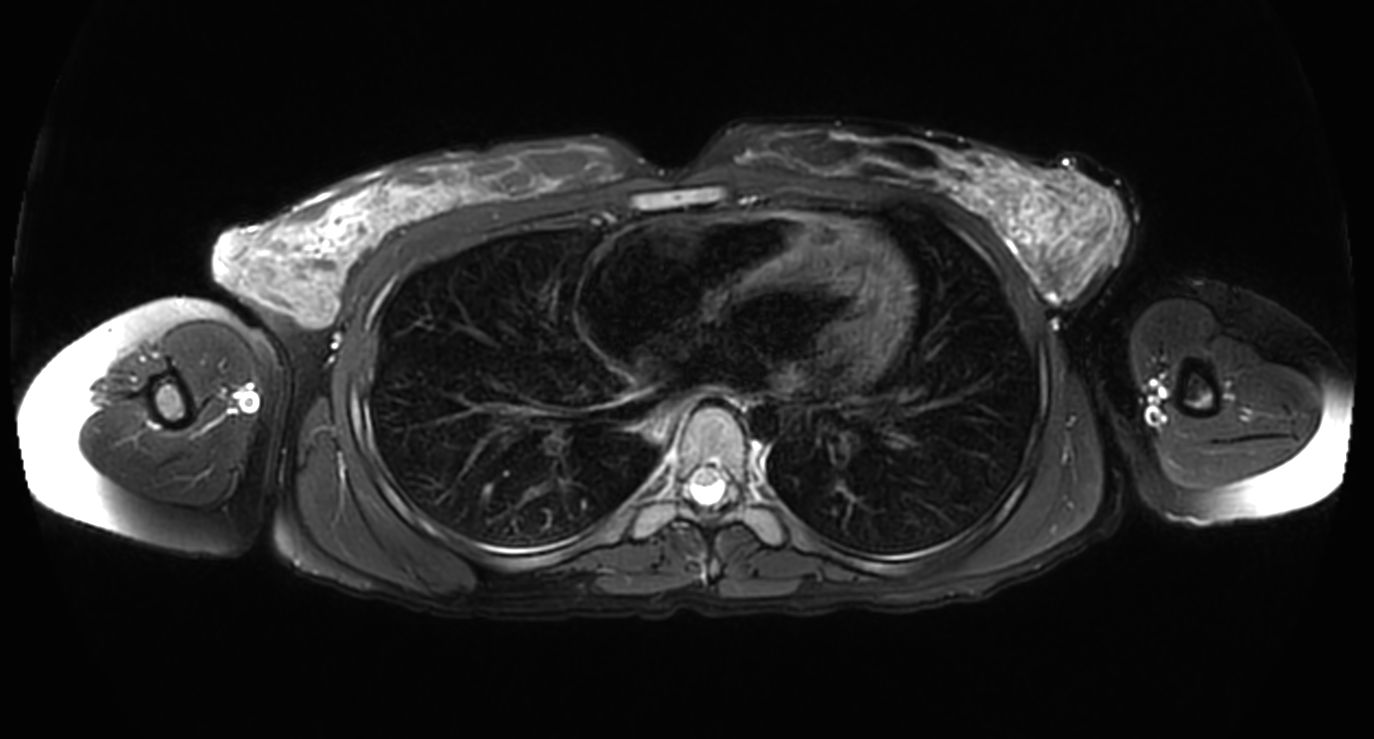

T1w mDIXON XD (Out Phase)